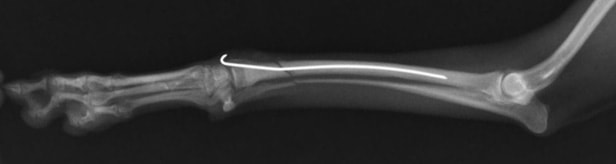

前肢の骨折:橈骨尺骨骨折

![]() 骨折時 |

![]() 手術後 |

![]() 骨折治癒 |

![]() 最後に金属の金具を取り除き完治 |